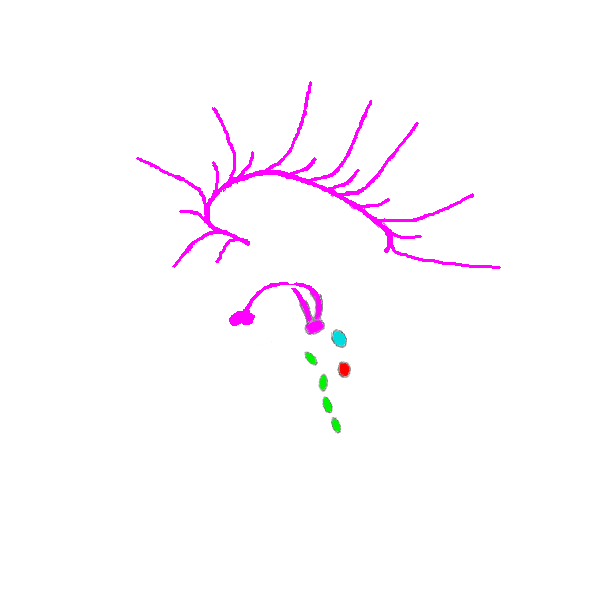

Het groene deel is de orbifrontale cortex (boven de oogkas), de secties voor de allerhoogste van alle hoge functies van het denken.

Het groene deel (boven) is de prefrontale cortex, de secties voor de hogere van alle hoge functies van het denken.

Het groene deel is de frontale cortex, alle secties waar de hogere functies van het denken zich bevinden. De locatie van de meer specifieke functies is slecht bekend, en de verdere indelingen zijn nogal variërend.